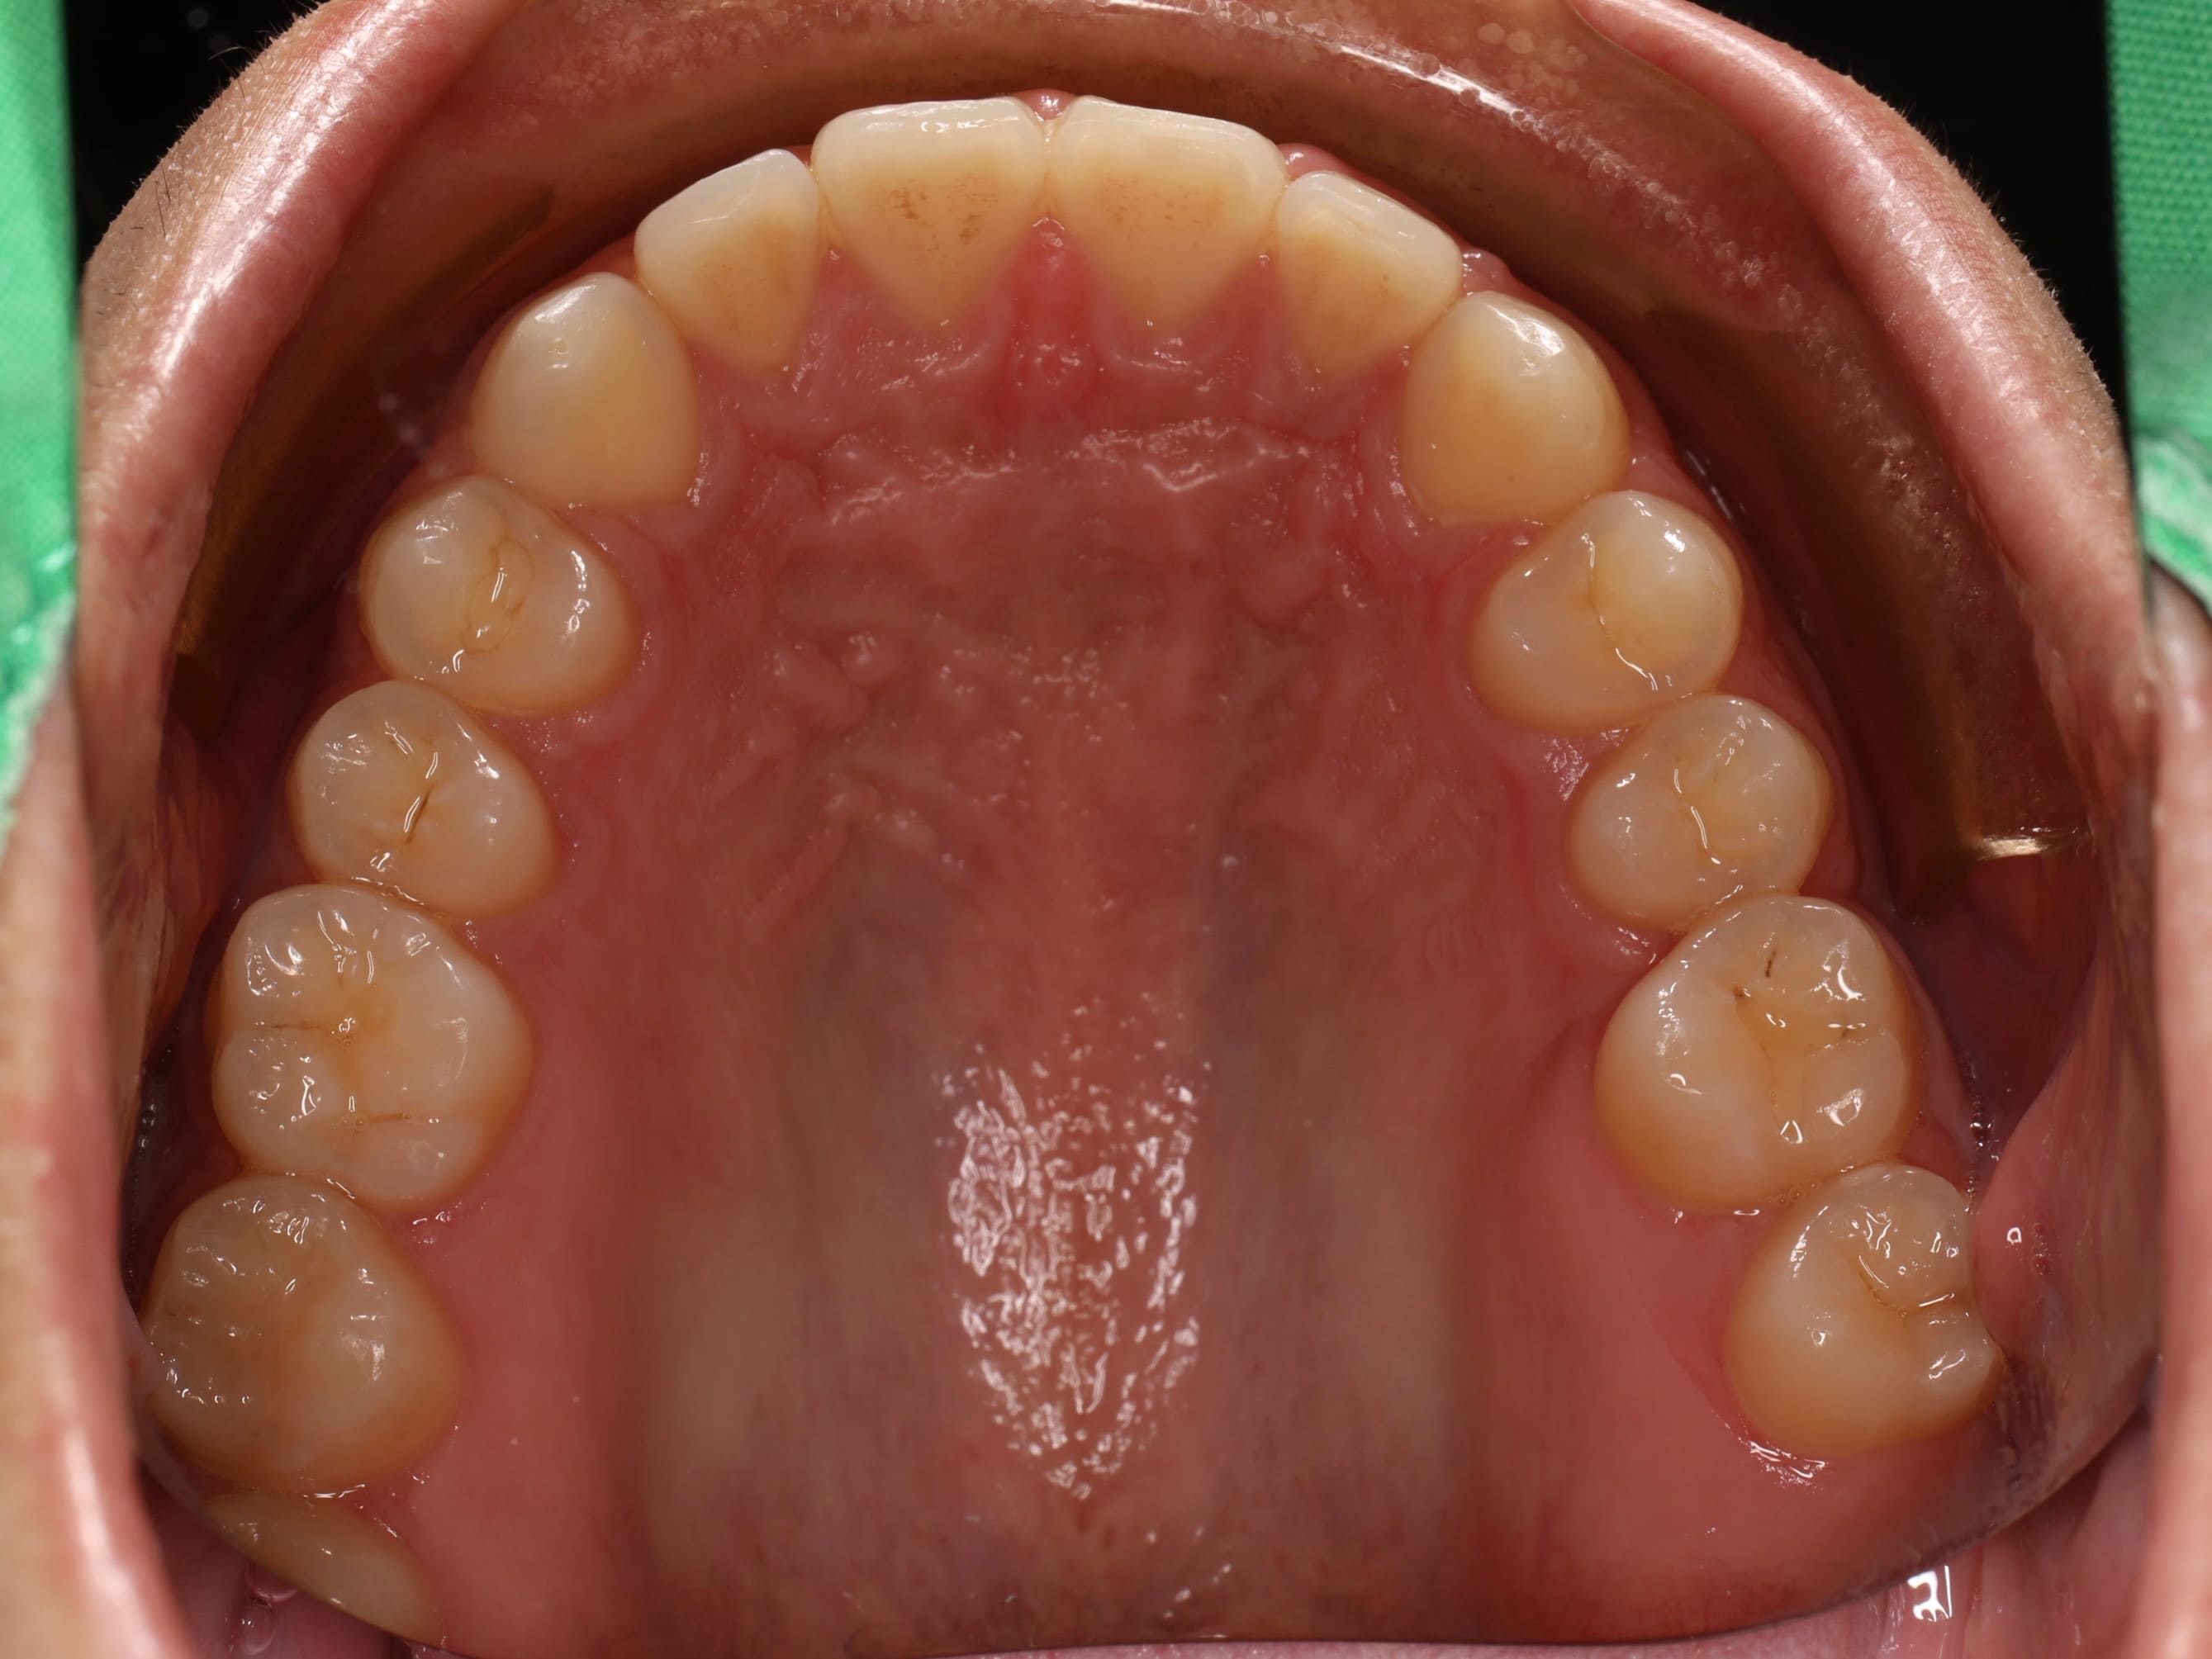

針對這些問題,我們擬定了完整的治療方案。首先,利用矯正的方式,將後方的第二大臼齒和智齒慢慢往前移動,填補缺牙的空間,同時調整上下排牙齒的咬合關係,讓錯咬的情況回復到正常的咬合狀態。當矯正治療完成後,病患的狀況其實已經改善了許多。

為了讓笑容更加完美,我們接著運用雷射方式進行微創的牙冠增長術,調整前牙美觀區牙齦的高度,讓牙齦和牙齒的比例更協調,整體笑容線條也更加自然。

完成所有療程後,病患的笑容真的煥然一新!不僅外觀上有了明顯的改變,整個人也變得更愛笑、更有自信了。